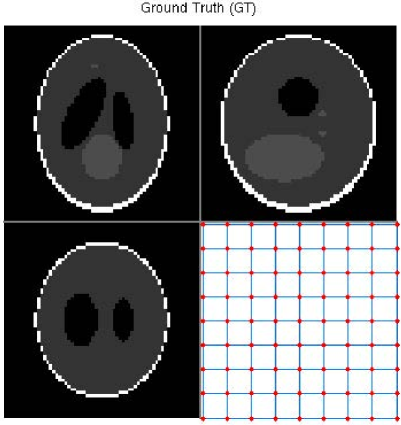

For the B-spline transformation model, we initially use a 3D Shepp-Logan phantom to test our simultaneous method. Figure 15(a) shows the 3D Shepp-Logan phantom (65×65×6565656565\times 65\times 65 in voxels), and also shows the central slice of each plane and the regular B-spline control point grid for the central slice of the transverse plane. The transformed phantom is shown in Figure 15(b), and illustrates the ground truth of the transformation. This ground truth deformation is simulated with the B-spline transformation model using 9×9×99999\times 9\times 9 control points randomly offset in each dimension.

In this experiment, we set different ranges of perturbation for each direction (x-, y- and z-axis), e.g., [Rangea,Rangeb]=[8,8]subscriptRangeasubscriptRangeb88[\mathrm{Range}_{\mathrm{a}},\mathrm{Range}_{\mathrm{b}}]=[-8,8], =[4,4]absent44=[-4,4], and =[2,2]absent22=[-2,2] (voxels) have been used respectively. Therefore, there are larger deformations for the in-plane slices and smaller ones for the out-of-plane. From the results shown in Figures 16(a) and (b), we can conclude that our simultaneous method has obtained an accurate reconstruction with a reasonable recovery of the non-rigid deformations. The montage views of the fixed, transformed, recovered, and difference images are shown in Figures 19, 20, 21, and 22.

Refer to caption

Figure 15: (a): Original fixed 3D Shepp-Logan phantom and its regular grid for the central slice; (b): Transformed 3D Shepp-Logan phantom and its deformed grid for the central slice, i.e., ground truth of the transformation. (Four sub-figures from top to bottom and from left to right are: Transverse view; Coronal view; Sagittal view; Grid of the central slice of the transverse view.)